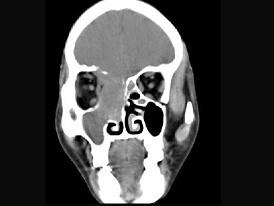

问题 女性,53岁,右侧鼻腔流血近一年,近来头痛,行CT检查如图所示,请选择正确的答案 ( )

选项 A、鼻腔炎性假瘤 B、鼻腔内血管瘤 C、鼻腔内息肉 D、副鼻窦炎 E、鼻腔癌

答案 E